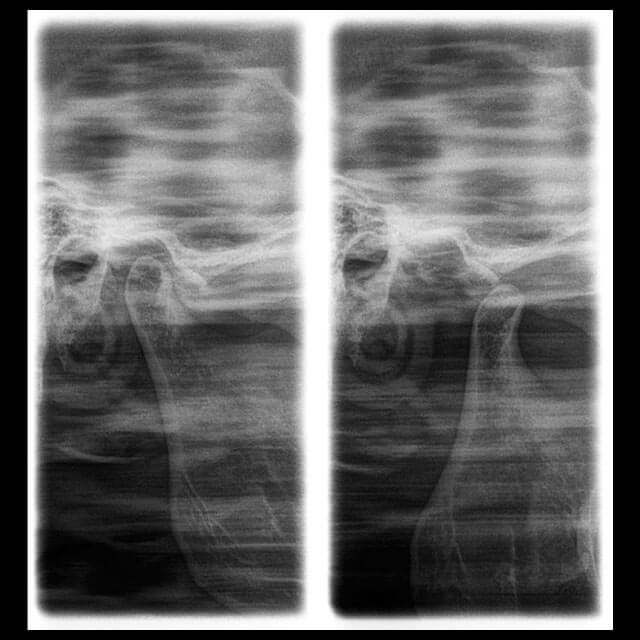

A Radiografia Transcraniana é uma técnica de diagnóstico por imagem que possibilita a análise da ATM (Articulação Temporomandibular). Esta técnica radiológica é de extrema importância, pois a região da ATM pode interferir em quase todas especialidades da odontologia.